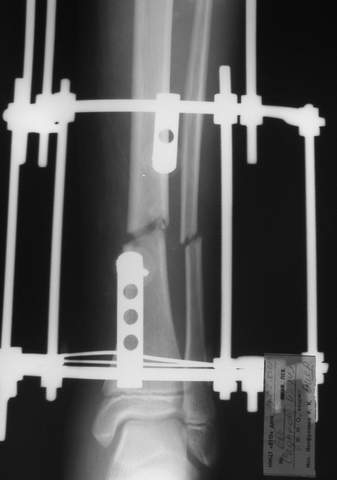

Под рукой прилагаемый пример. Как видите, "стриптиз-аппарат" (шутка проф. З.К.Башурова): 3 кольца-2 кольца-2 полукольца. В случае, который представил Евгений, характер повреждения позволил бы сразу использовать аппарат на основе 2 колец; в крайнем случае прокс. опора м.б. демонтирована сразу после репозиции.

В аттачтах №№ 1 и 2 - примеры, когда 2 кольца не позволили послеоперационно

исправить смещение фрагментов большеберцовой (по ширине и вальгусное).

А казалось бы (#2) - поиграй на штангах и все влетит.

1

1a